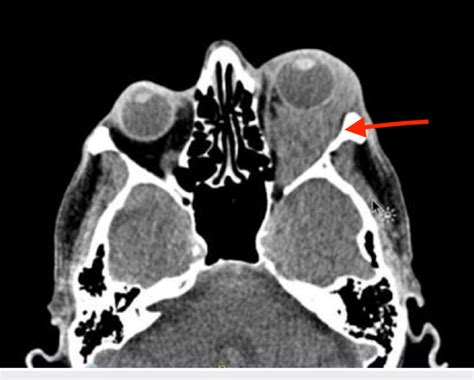

Paciente de 23 años, que tras sufrir un traumatismo facial izquierdo, presenta herida subpalpebral que fue suturada en urgencias, fractura de arco cigomático con hundimiento del mismo y fractura órbito-malar sin desplazamiento. De acuerdo con el paciente, se decide realizar tratamiento, de forma programada, de la fractura de arco cigomático mediante reducción cerrada con gancho de hueso. Dos días después de la fractura y bajo anestesia general, se incide con bisturí frío sobre la zona de la fractura, se introduce el gancho de hueso y una vez colocado por debajo de la fractura del arco, se realizan maniobras de tracción del arco cigomático para su reducción, tras varias manipulaciones se aprecia proptosis aguda con dificultad para la retropulsión del globo ocular izquierdo y hernia conjuntival izquierda.

Proptosis aguda y hernia conjuntival izquierda tras la manipulación quirúrgica.

Como complicación de las maniobras quirúrgicas y/o movilidad de los focos de fractura, aparece un hematoma orbitario, que decidimos drenar de forma urgente, en el mismo acto quirúrgico, mediante una incisión en fondo de vestíbulo oral, desperiostización, apertura del seno maxilar mediante punción con una pinza tipo Crile, sin esperar al montaje y puesta en marcha del micromotor quirúrgico, e introducción de la cánula de aspiración a través de la apertura ósea, rápidamente se aprecia la aspiración de sangre y la resolución del hematoma, disminuyendo la proptosis y la hernia conjuntival. Colocamos un drenaje intraoral.

Conociendo la anatomía de la órbita, entendemos su falta de flexibilidad y, por tanto, pequeños hematomas ya pueden crear un "síndrome compartimental" con aumento de la presión intraorbitaria, exoftalmos, compresión vascular y/o del nervio óptico de dramáticas consecuencias. Los signos que avisan intraoperatoriamente de un hematoma orbitario son: proptosis aguda con dificultad para la retropulsión, inflamación/hematoma periorbitario y dilatación de la pupila.